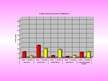

Hroniski obstruktīvas plaušu slimības